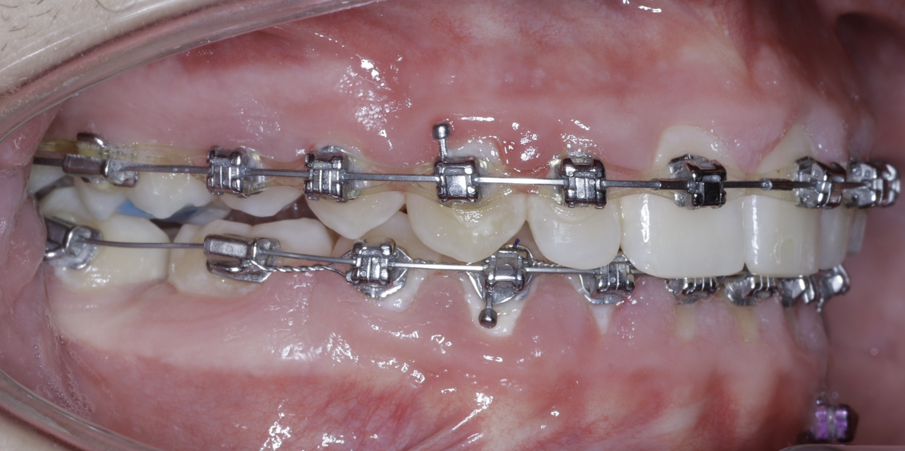

TADs are placed at the second visit with a 14 × 25 mm copper (Cu) and nickel–titanium (NiTi) wire and are tied from the anchor to the wire with an elastic thread (surgical thread; Fig. 6). Once the patient has progressed to larger Cu–NiTi wires and stainless steel, the TADs are tied to the wire using a power chain looped to the wire, or NiTi closing springs, depending on the thickness of the tissue (Figs. 7 & 8).